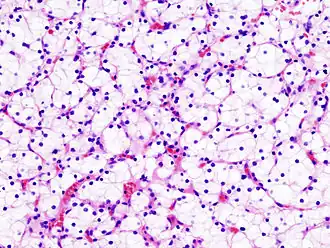

Macroscopisch onderzoek (onderzoek met het blote oog) toont een gelige, multilobulaire (meerlobbige) tumor in de nierschors met vaak zones met necrose (afgestorven weefsel), bloeding en verlittekening.

Bij licht-microscopisch onderzoek is te zien dat de tumorcellen samenklonteren tot strengen, papillen, buisstructuren of nestjes. De individuele cellen zijn atypisch (afwijkend van de normale structuur van de niercel), polygonaal (veelhoekig) en groot. Omdat de cellen glycogeen en lipiden opslaan in het cytoplasma zien ze er helder (Engels: clear), vetbeladen uit; de celkern blijft centraal in de cel, de celmembraan is duidelijk zichtbaar. Sommige cellen zien er kleiner uit met eosinofiel cytoplasma en lijken op normale tubuluscellen. Het stroma, het omringende bindweefsel van het gezwel, is verminderd, maar wel gevacuoliseerd (met vacuolen). De tumor drukt op het omringende parenchym van de nier en vormt een pseudokapsel.[24]